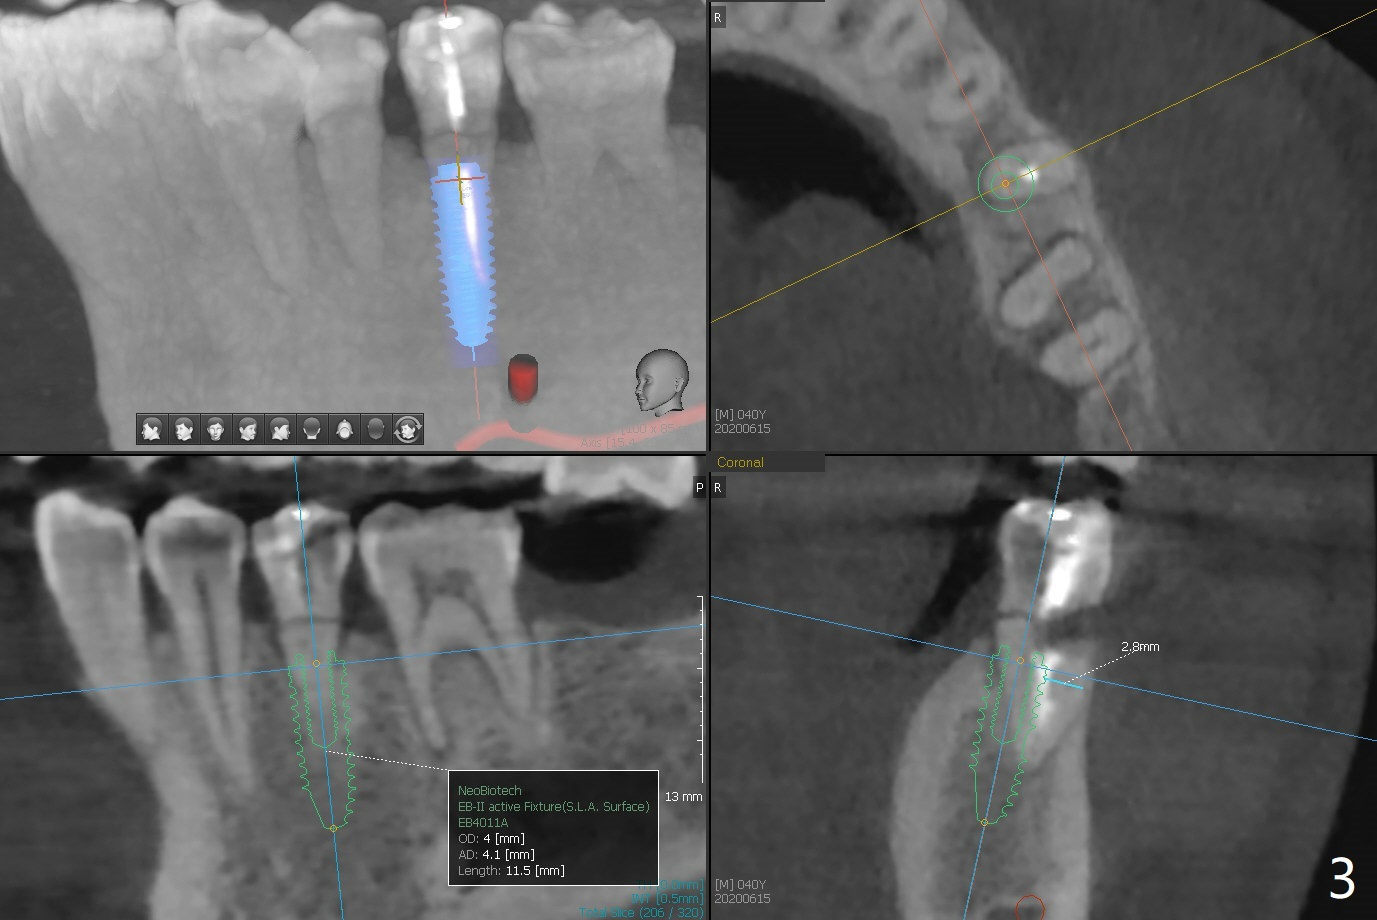

A 40-year-old man with #18 missing and #31 residual roots just fractures the tooth #20 (Fig.1). After discussion, he agrees to have implants at #18 and 20 first. To prevent buccal drifting of osteotomy and implant at #20, the implant will be placed lingual, but it does not contact the lingual plate (Fig.2-4). Traditionally, the whole tooth needs to be extracted (Fig.5,6) before initial osteotomy (Fig.7 red). The latter has tendency to drift buccal because of the lingual slope (Fig.7 arrow). To prevent the drifting, the crown of the tooth is removed (Fig.8). A guide is fabricated with 12 mm offset so that after bone trimmer (Fig.9 pink), the following drills have more contact with metal sleeve. Furthermore the drills will have less chance of buccal shifting because of the presence of the root.